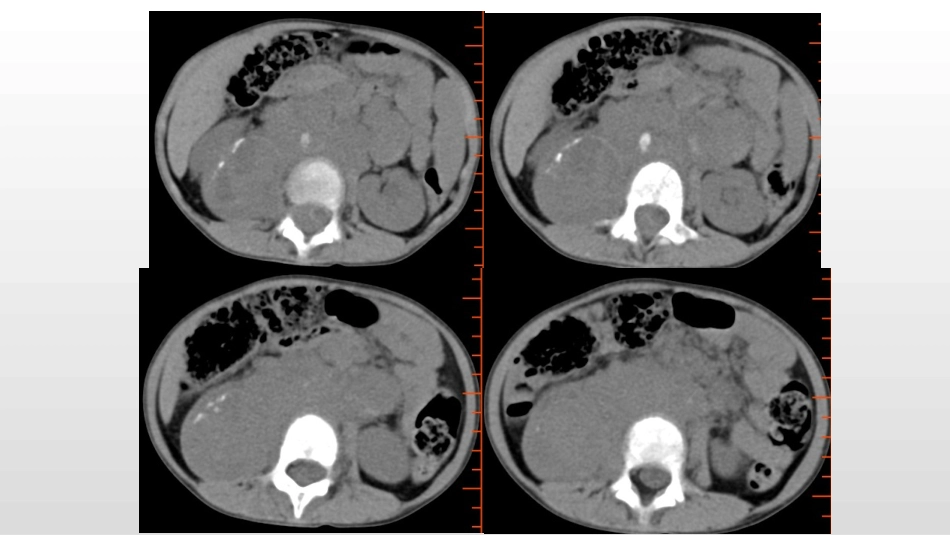

腹膜后神经母细胞瘤在此输入您的封面副标题病例3•男,6y•门诊患者,发现腹部肿块•病理:神经母细胞瘤腹膜后神经母细胞瘤(RNB)临床要点:RNB是一种胚胎性肿瘤,来源于未分化的交感神经节细胞,是小儿最常见的恶性实体肿瘤之一。肾上腺、腹膜后脊柱旁、后纵隔、盆腔和颈部都可发生。发生于腹膜后的NB约2/3位于肾上腺髓质。临床上以5岁以下小儿多见,一般情况较差,贫血貌,可有发热,较早出现转移,表现为头部包块、眼球突出、肝大、四肢痛等。90%-95%尿香草扁桃酸(VMA)和高香草酸(HVA)升高,是诊断本病的重要指标。腹膜后神经母细胞瘤(RNB)•影像要点:•CT:75%-80%患者出现钙化,其中沙砾状钙化较为特征。瘤体向周围浸润生长,易侵犯肾脏,并包绕大血管及其主要分支,称为“血管包埋征”,是与其他腹膜后恶性肿瘤不同之处,增强扫描不均匀强化,可更清晰显示大血管包埋征。病变早期就可侵犯周围淋巴结,可见淋巴结肿大或钙化。远处转移可发生于骨、头颅、肝、皮肤、胸部等。•MR:T1WI上肿瘤信号常低于或与肝实质相似,T2WI上肿瘤信号较高且不均匀。转移灶在FSEIR序列上呈高信号,增强T1WI脂肪抑制序列可见转移灶呈斑片状强化。鉴别诊断•肾母细胞瘤:原发于肾,增强CT可见肾皮质出现“残肾征”,残余肾直径常大于正常肾直径,肾盏多破坏扭曲拉长变形。钙化发生率较NB低,对周围血管以推挤为主。鉴别诊断•神经节细胞瘤:与本病同源,好发部位相近,密度均匀,很少出现囊变坏死,对周围血管以推挤为主。鉴别诊断•腹膜后脂肪瘤•畸胎瘤小结•腹膜后神经母细胞瘤一般不难诊断,肿瘤发生于肾上腺区或椎旁交感神经链时,影像学通常可以观察到血管包埋、早期淋巴结转移(尤其是膈脚后淋巴结转移)、肿瘤跨越中线、钙化等特征性表现。MR对本病分期诊断明显优于CT。